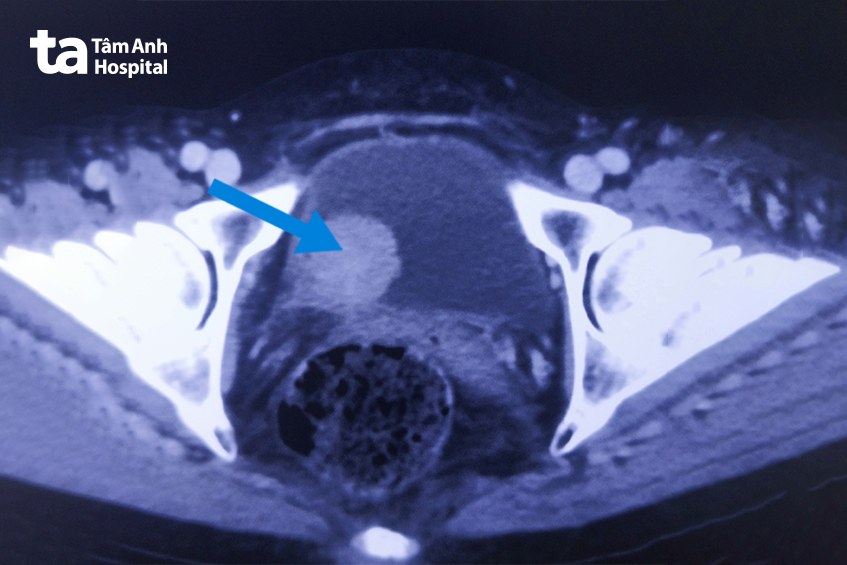

Thạc sĩ bác sĩ Nguyễn Tân Cương, Phó khoa Tiết niệu, Trung tâm Tiết niệu – Thận học – Nam khoa, Bệnh viện Đa khoa Tâm Anh TP.HCM, cho bà nội soi bàng quang, chụp cắt lớp vi tính (CT Scan) vùng bụng chậu để đánh giá chính xác giai đoạn của khối u bàng quang. Kết quả xác định bà chỉ có 1 khối u ở thành phải, ung thư còn khu trú trong bàng quang, chưa xâm lấn ra ngoài, chưa có dấu hiệu di căn.